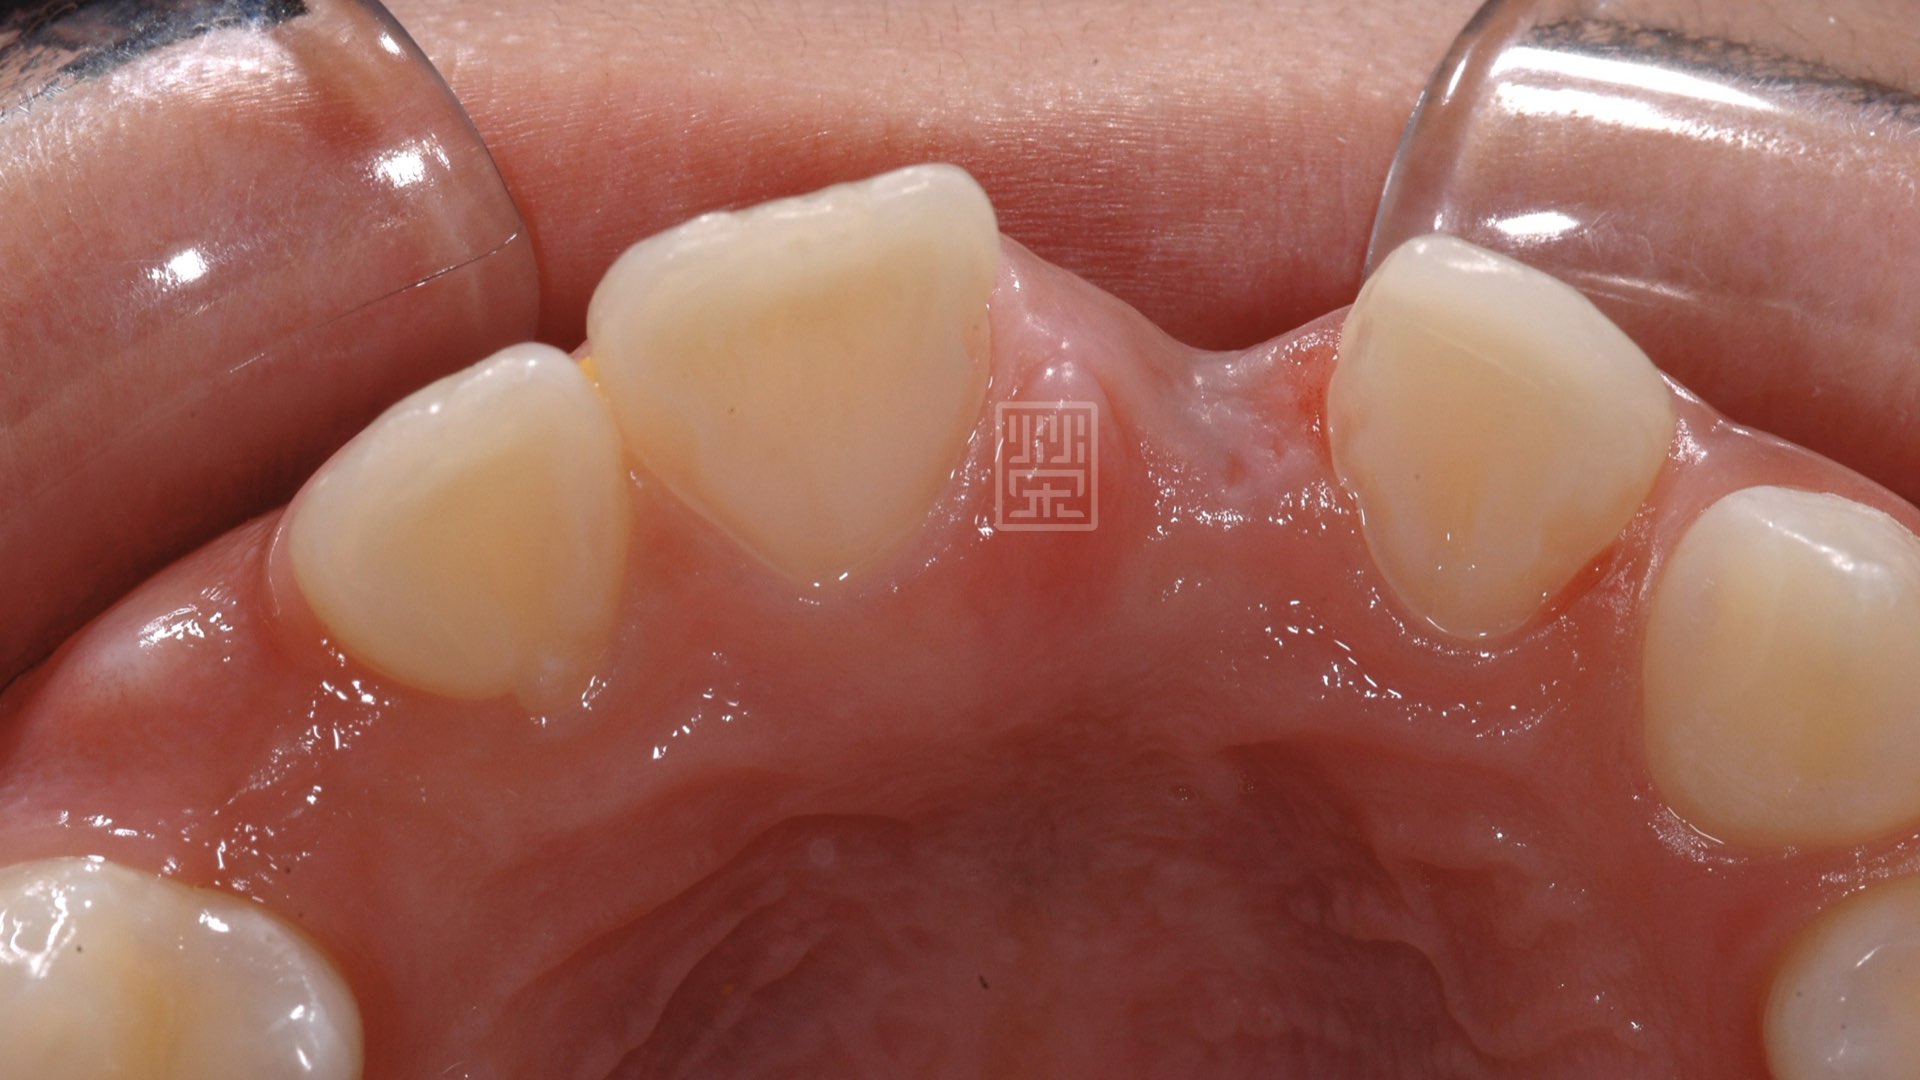

初次補骨

植牙與再次補骨